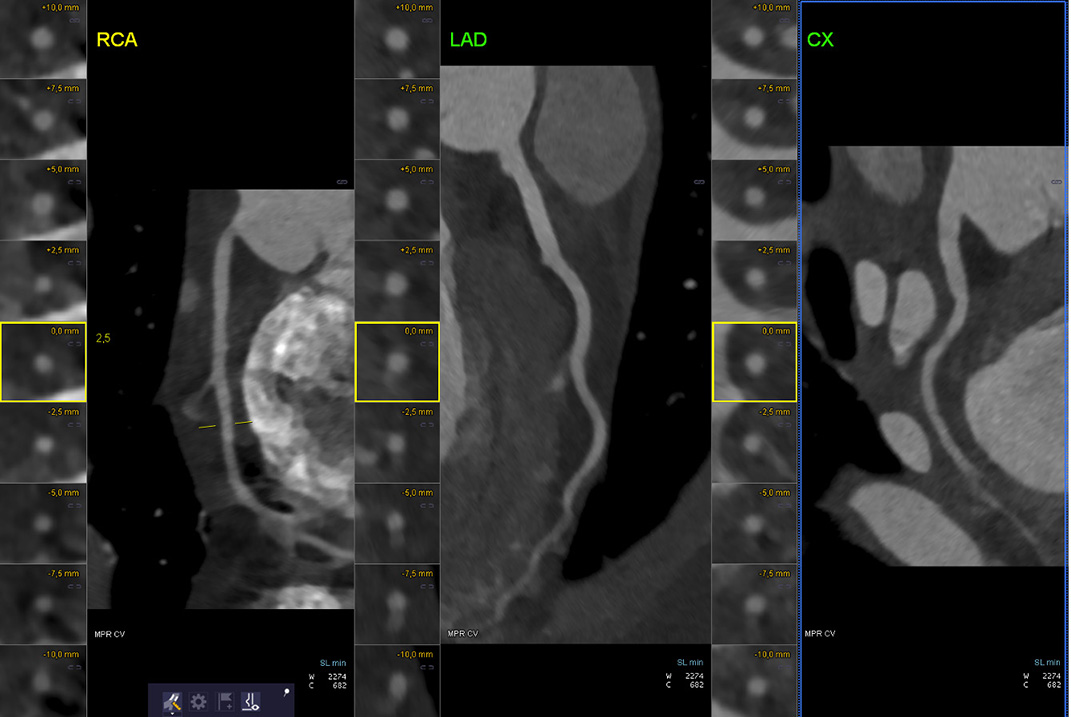

Devant des arguments forts pour un tableau de syndrome coronarien aigu, une coronarographie est réalisée.

Cette dernière retrouve une lésion monotronculaire sur occlusion aiguë de l'artère circonflexe proximale d'allure thrombotique (image 1 et 2).

Une thrombectomie productive permet un succès de revascularisation sans pose de stent (image 3). Il existe malheureusement une embolisation distale dans l'artère circonflexe et dans la première artère marginale (image 4).

Un bilan exhaustif de pathologie cardio-embolique est réalisé et un scanner cardiaque retrouve une auricule gauche libre de thrombus (pas d'argument pour une fibrillation atriale) avec des artères coronaires d'implantation physiologique et un score calcique nul, ce qui écarte à priori un processus athérosclérotique.